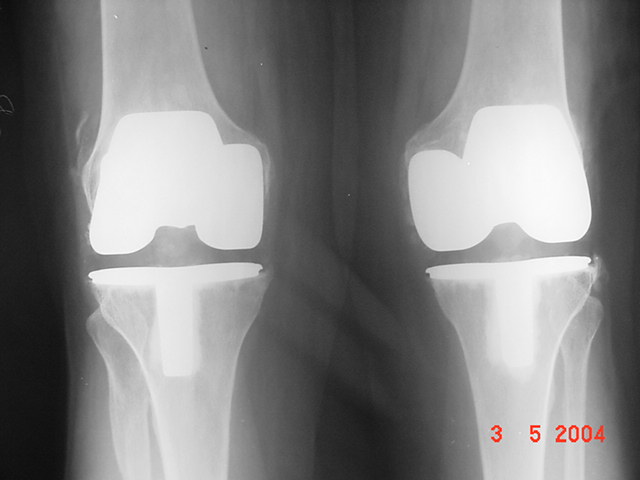

Paciente del sexo femenino de 79 años de edad.

Por artrosis de rodilla prótesis total bilateral.